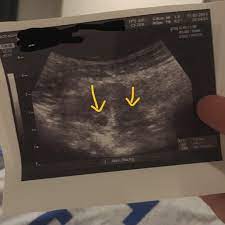

2 Fruchthohle Auf Ultraschall Ubersehen Schwangerschaft Gynakologie Zwillinge

Erstes Us In 5 Ssw 2 Fruchthohlen Forum Schwangerschaft Urbia De